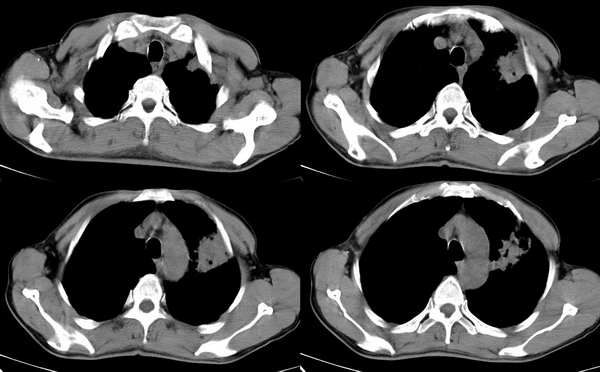

男,58岁,咳嗽1月加重1周,伴痰中带血

ct:左上肺块状影、其内徐点状气体外蜜度大致均匀。周围粗大索状影

其内透光影仔细观察像是支气管,病灶周围有渗出改变,该病灶不考虑感染性病变,机化性肺炎能排除吗

理由:1 病灶有恶性肿瘤的特征:空泡征,毛刺,棘状突起

左上肺病灶与胸膜脂肪线存在,未见明显胸膜凹陷征,虽然病灶边缘不规则,但未见明显“短毛剌、切迹征、免耳征、血管束集征”,其间亦见条索状、斑点状影,认为左上肺结核或炎性病变>周围型肺癌。

ct:左上肺块状影、其内徐点状气体外蜜度大致均匀。周围粗大索状,肺结核.